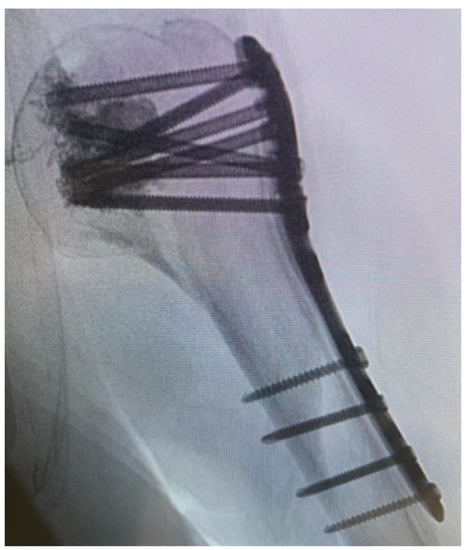

After a minimally invasive delta split procedure, traction sutures were applied through the rotator cuff. A reduction was achieved by the traction and manipulation of the sutures. In some cases, a reduction was achieved by the direct manipulation of the humeral head through the fracture. After a provisional fixation was achieved with 1.6 mm K-wires, the plate was placed and fixed with four to seven screws in the head and three screws in the diaphysis (Figure 2).

Figure 2. Plate placement, temporary fixation with K-wires and implantation of a cortex screw.